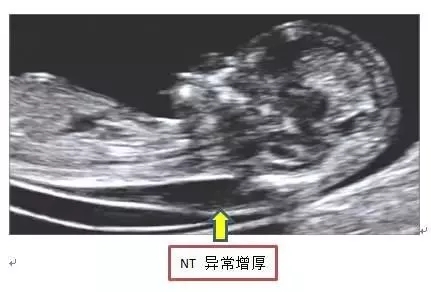

胎儿颈项透明层简称NT,指胎儿颈后部皮下组织内液体积聚的厚度,目的是为了在妊娠较早阶段诊断染色体疾病和发现多种原因造成的胎儿异常。

颈后透明带通常随胎儿的生长而增长,在孕14周后会逐渐消失。一般正常参考值为<2.5MM,由于个体情况不同,一些正常胎儿的体液也较多,容易影响测量结果。所以颈后透明带较厚,并不意味着胎儿一定有问题,各位宝妈要听医生的解读判断哦~NT检查看得出风险高低,不代表最终结果,所以对待NT增厚的正确态度是不焦虑、不忽略。